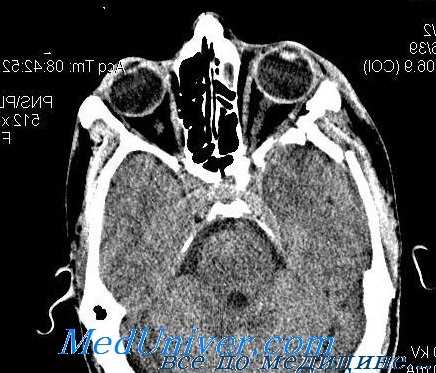

Такое состояние может быть опасно для жизни, при симптомах сердечной блокады рекомендуется провести ЭКГ-исследование. Корональная КТ может выявить «отсутствие» нижней прямой мышцы при практически нормальном дне глазницы с локализацией мышцы в верхнечелюстной пазухе. Томограммы могут быть интерпретированы как нормальные, в таком случае необходимо получить мнение нескольких специалистов. При таком переломе может быстро развиться ишемия нижней прямой мышцы с ишемическим некрозом, следствиями которого будут фиброз и потеря функции мышцы. Следовательно, операцию рекомендуется провести в пределах 24—72 часов для предотвращения некроза мышцы и уменьшения риска тяжелой брадикардии вследствие развития окулокардиального рефлекса.